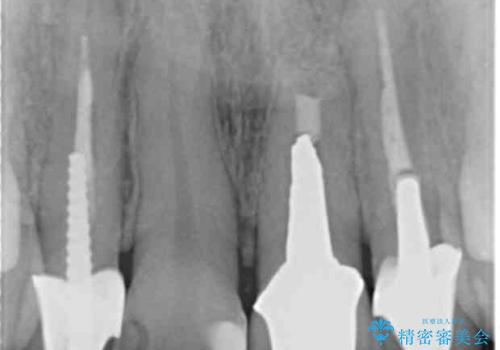

- 前歯のクラウンの歯肉の位置が年々変化し、歯ぐきのフチが黒くなってしまった、綺麗にしたいと希望されて来院されました。

装着されているセラミッククラウンを除去したのち、現在の歯ぐきのラインにしっかりと合う精度の高いオールセラミッククラウンを作製していきます。

- 39.6万円(ジルコニアクラウン×3・仮歯×3)費用は治療当時の料金となります